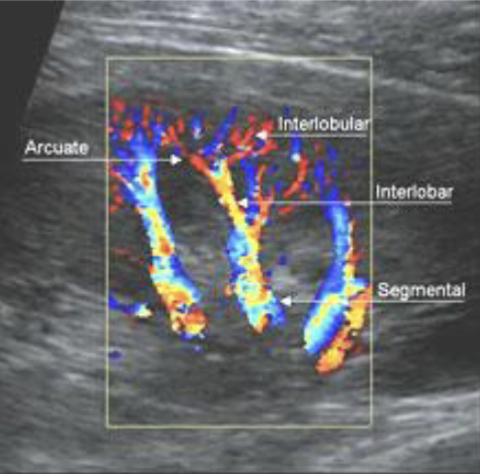

renal pyramids

renal artery

vascular supply

renal parenchyma